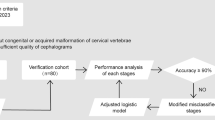

In order to balance the sample size of each CVS, the redundant lateral cephalograms were removed. Finally, we established a data set with 10,200 samples; each CVS had 1700 samples. 70% are used as the training set for training the CVM assessment system called the psc-CVM assessment system, 15% as the validation set for tuning the hyperparameters of the system, and 15% as the test set for evaluating the performance of the system, and they are independent of each other without overlap. The entire process in this part is briefly presented in Fig. 1.

The entire process of Data set creation and distribution. a A total of 15,000 lateral cephalograms were collected from patients admitted to the Department of Orthodontics of Shanghai Ninth People's Hospital. The CVS of each lateral cephalogram was determined by expert panel. Finally, a data set with 10,200 samples was established, and each CVS had 1700 samples. b 70% of the data set is used as the training set, 15% as the validation set, and 15% as the test set, and they are independent of each other without overlap